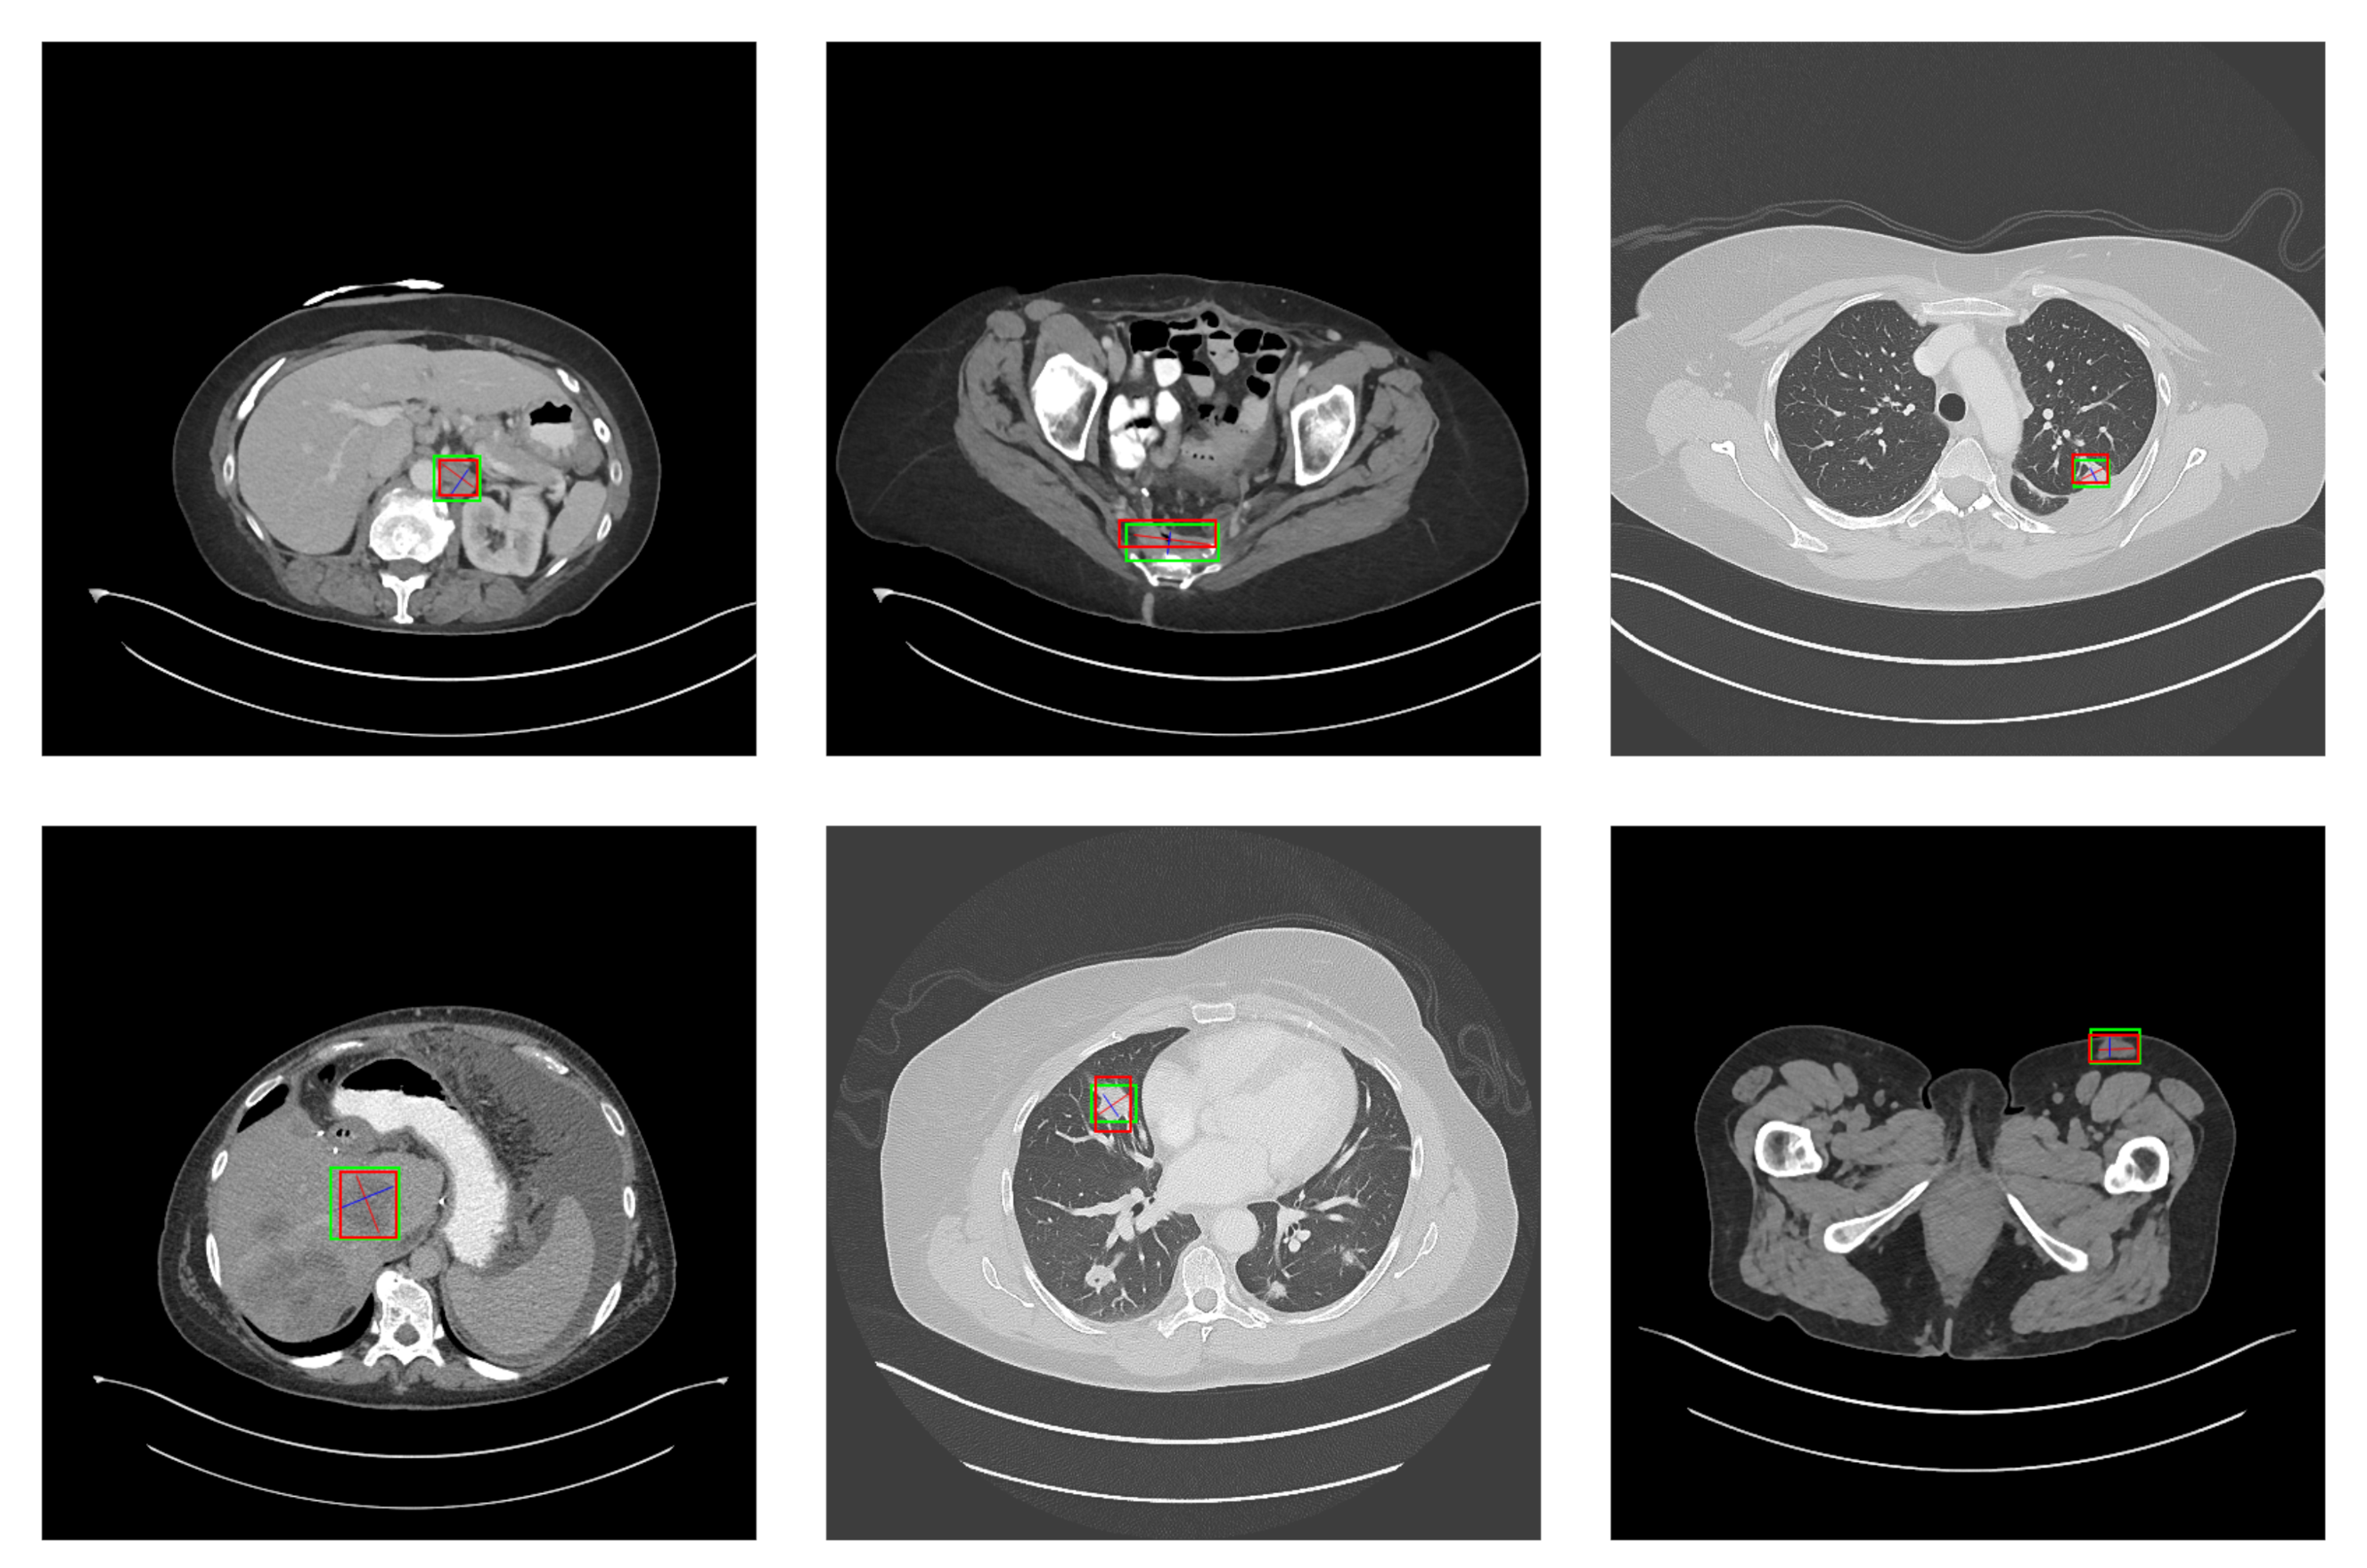

5.2. Detection Results

For further comparison, we extracted six images from the CT image series of DeepLesion. These images were taken from different sites of lesions and different areas of lesions, showing the detection results of the comparison model as comprehensively as possible. Figure 10, Figure 11, Figure 12, Figure 13, Figure 14, Figure 15, Figure 16, Figure 17, Figure 18 and Figure 19 show the detection results. All green boxes represent ground truth; red boxes denote predicted bounding boxes. It can be seen that Faster-RCNN performs very poorly on small lesions and lesions that are not easy to identify, while YOLO v3, YOLO v4, and SSD series perform relatively well. However, the aspect regression of the bounding box at small lesion locations is still not accurate. On the other hand, EfficientDet, Mask-RCNN, and YOLO v5 perform relatively well and detect lesions accurately. This may be related to the attention extraction module in these networks.

Figure 12.

The detection results of YOLO v5 in the DeepLesion dataset. The green box marks the location of the lesion.

Our model, especially SGDN 512, outperforms the previous models by detecting lesions with high accuracy for non-minimal lesions. Although there is still room for improvement, it has outperformed other models. On the one hand, we augment the image with the GAN model before it is fed into the backbone. On the other hand, we add the GAN model to the attention extraction module of the model, which can significantly improve the model’s robustness.

According to Figure 10, Figure 11, Figure 12, Figure 13, Figure 14, Figure 15, Figure 16, Figure 17, Figure 18 and Figure 19, the proposed model produces the most comprehensive detection results compared to other models. However, there are still a few cases where the shortcomings of SGDN can be seen: the arrows in Figure 19 show that our model is still not accurate at the edge of the lesion. In addition, from these figures, we can see that all the comparison models perform very poorly at the site of arrow A. The difference between the predicted box and the ground truth given by our model at arrow A is the largest compared to other recognition results.